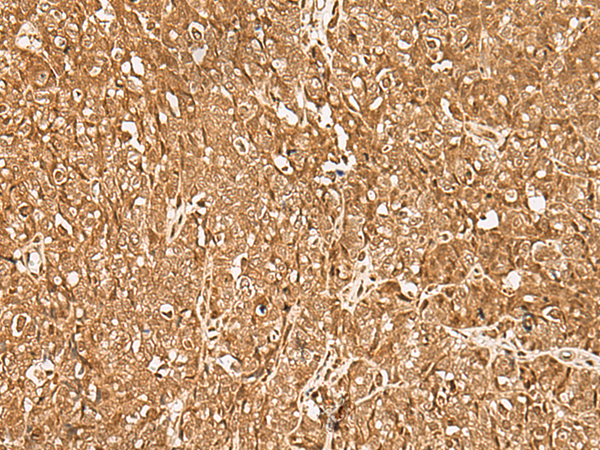

IHC positive control: |

Human ovarian cancer and Human thyroid cancer |

IHC Recommend dilution: |

40-200 |